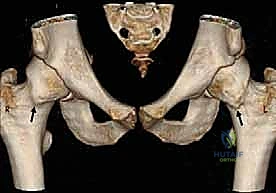

- الأشعة المقطعية ثلاثية الأبعاد (3D CT Scan): في الحالات المعقدة، يتم بناء نموذج ثلاثي الأبعاد لورك المريض، مما يسمح للدكتور هطيف بالتخطيط الجراحي المسبق ومعرفة مقدار العظم الذي يجب إزالته بدقة المليمتر.

- انحشار الكامة (Cam Impingement): يحدث عندما لا يكون رأس عظمة الفخذ كروياً بشكل مثالي. وجود نتوء عظمي إضافي على شكل "كامة" يؤدي إلى احتكاكه بحواف التجويف عند ثني الفخذ، مما يقشر الغضروف ويمزق الشفا.

- انحشار الكماشة (Pincer Impingement): يحدث عندما يمتد عظم التجويف الحقي بشكل مفرط ليغطي رأس الفخذ أكثر من اللازم، مما يسحق الشفا الحقي بين العظام مثل الكماشة أثناء الحركة.

- الانحشار المختلط (Mixed Impingement): وهو الأكثر شيوعاً، حيث يعاني المريض من كلا التشوهين (الكامة والكماشة) في نفس الوقت.